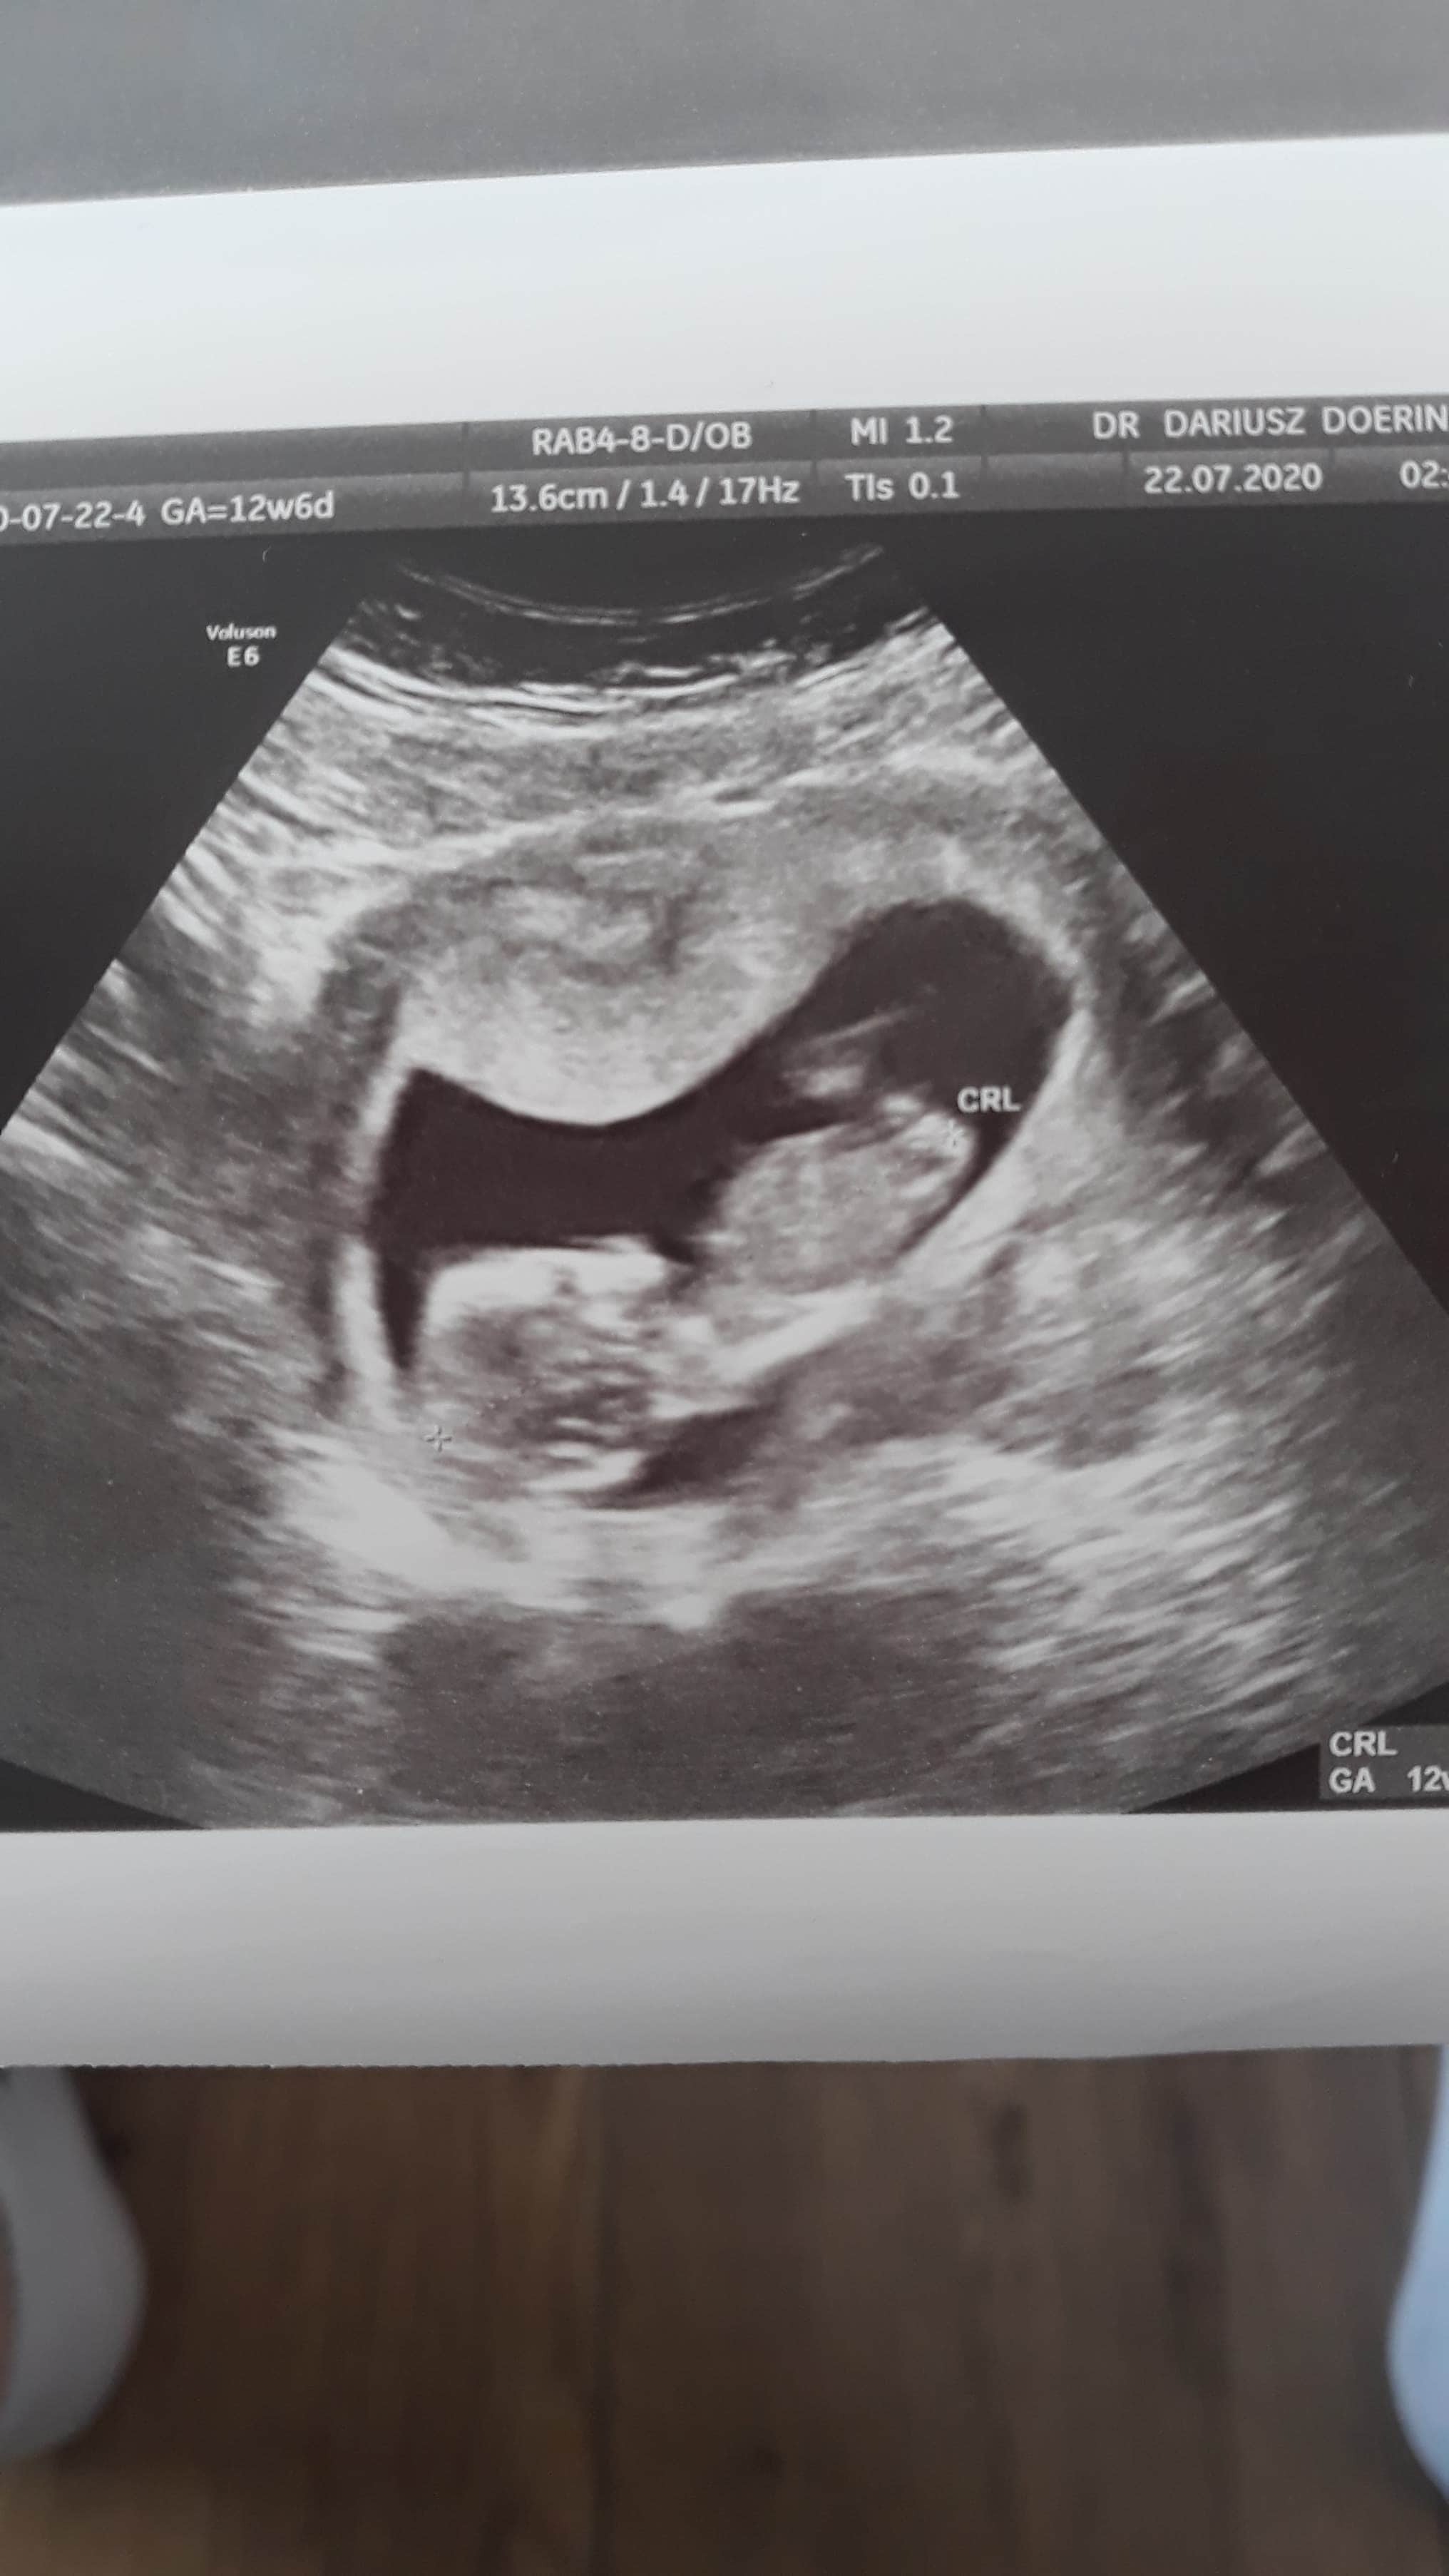

Cześć dziewczyny,

Jak obstawiacie - chłopiec, czy dziewczynka? :)

Załączniki

• IMG_20200715_132028.jpg

IMG_20200715_132028.jpg

1,1 MB · Wyświetleń: 195

• 15948122551844865087328945464018.jpg

15948122551844865087328945464018.jpg

1,1 MB · Wyświetleń: 177